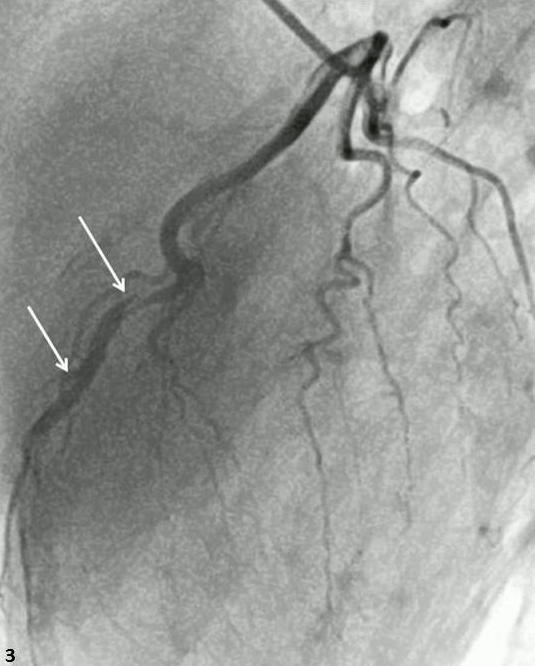

Abstract PDF ECG 1 Angio 1 Angio 2 Angio 3 Angio 4 ECG 2 Table Chart Original File 1 2 3 4 5 6 Reply to reviewer Fig. 1. ECG during myocardial infarction Fig. 2. Coronary angiography of LCA during myocardial infarction Fig. 3. Coronary angiography of LCA during myocardial infarction Fig. 3a. Coronary angiography of LCA during myocardial infarction Fig. 4. Coronary angiography of LCA 2 years after myocardial infarction Fig. 5. Coronary angiography of LCA 2 years after myocardial infarction Fig. 6. ECG 2 years after myocardial infarction Fig. 7. Thrombolytic trials in patients with coronary artery dissection Fig. 8. Flow chart of the study selection process -